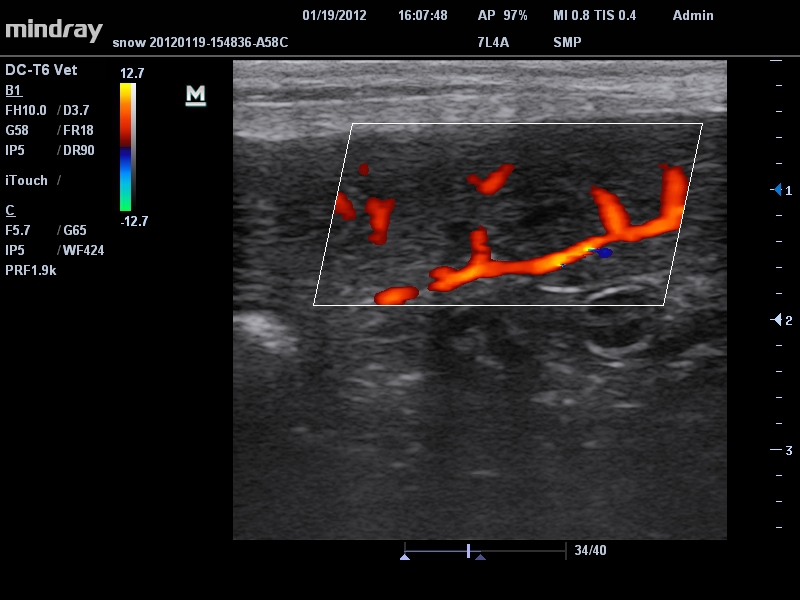

Ветеринария:

Да

• Линейный ультразвуковой датчик Mindray 7L4A

• Режимы сканирования: B/M/CFM/PDI/Направленный PDI/PW, HPRF, Тканевая гармоника, М- и цветной М-режим.